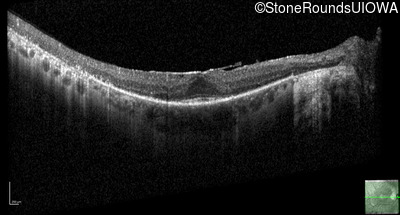

Visit at age: 58 years

Optical Coherence Tomography - Right - 20/25 -3

Exemplar / OCT Stack